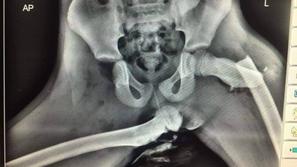

Razvada Samo pokažite mu to fotografijo ... Šokantna rentgenska fotografija izpahnjene stegnenice, posledica nespametnega početja.